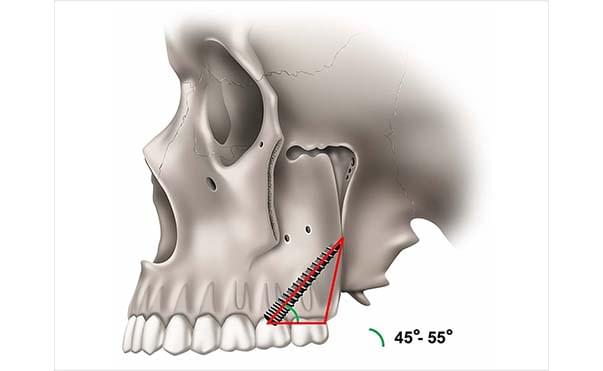

Pterygoid Implants